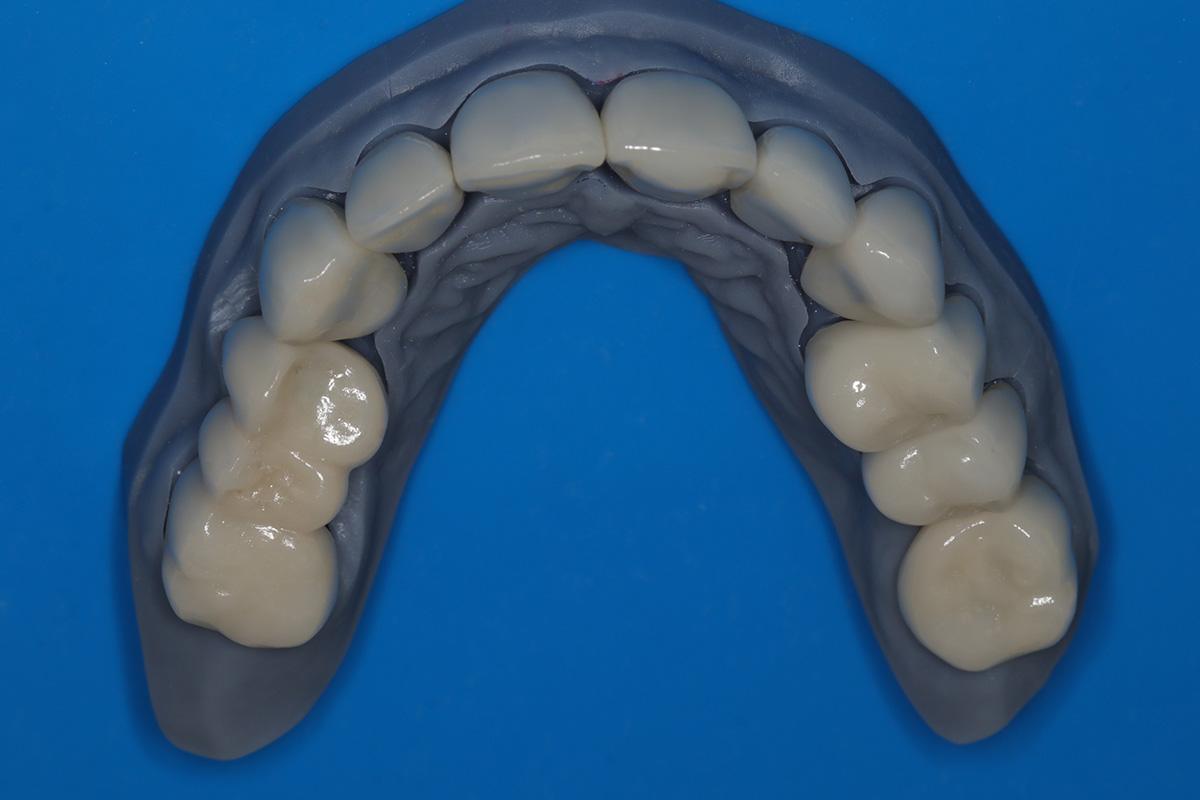

Następnie została wykonana wizualizacja nowego uśmiechu, idealnie dopasowana do twarzy Pacjentki. Po jej akceptacji, przygotowaliśmy komplet koron i licówek pełnoceramicznych na górne i dolne zęby.

Dzięki współpracy lek. stom. Michała Badowskiego i techn. dent. Joanny Gancarz z laboratorium Dentalscan Pacjentka zachwyca pięknym uśmiechem!

Przeprowadziliśmy precyzyjne leczenie implantologiczne, wszczepiając 11 implantów w szczęce i żuchwie. Konieczna była też regeneracja kości. Po 6 miesiącach gojenia nastąpiła odbudowa pełnołukowa. Kształt, kolor i ustawienie zębów zostały dobrane oraz wykonane na indywidualne życzenie Pacjenta.